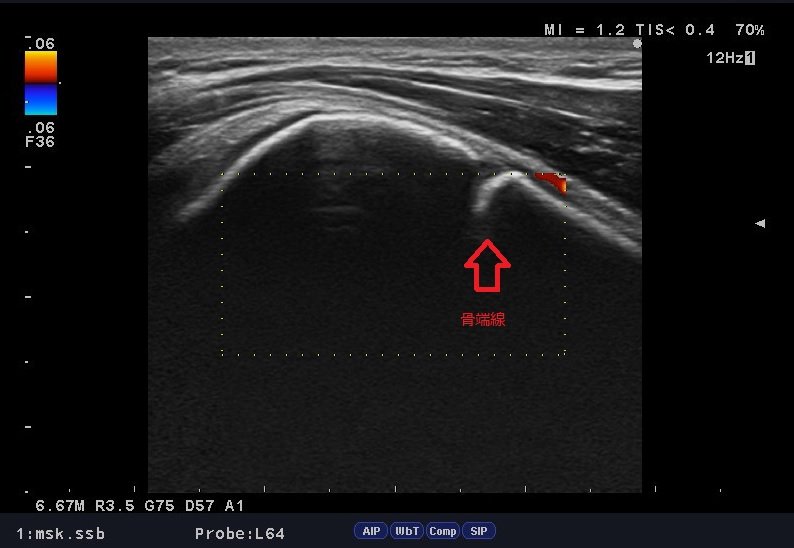

来院時、三角筋上に痛みを訴えており、肩インピンジメント症候群を疑いましたが、いろんな角度から徒手検査、触診、エコー検査、問診をおこなったところ「上腕骨近位骨端線損傷」の可能性が疑われました。

簡単に言えば、上腕骨の成長軟骨の損傷で、またの名を「リトルリーガーズショルダー」とも呼ばれます。

上腕骨近位骨端線損傷とは投球動作、バレーのスパイク、テニスのスマッシュなど、成長段階にある上腕骨に、引っ張りやねじれのストレスが繰返し加わり、上腕骨近位の骨端線が離開する状態のことを言います。